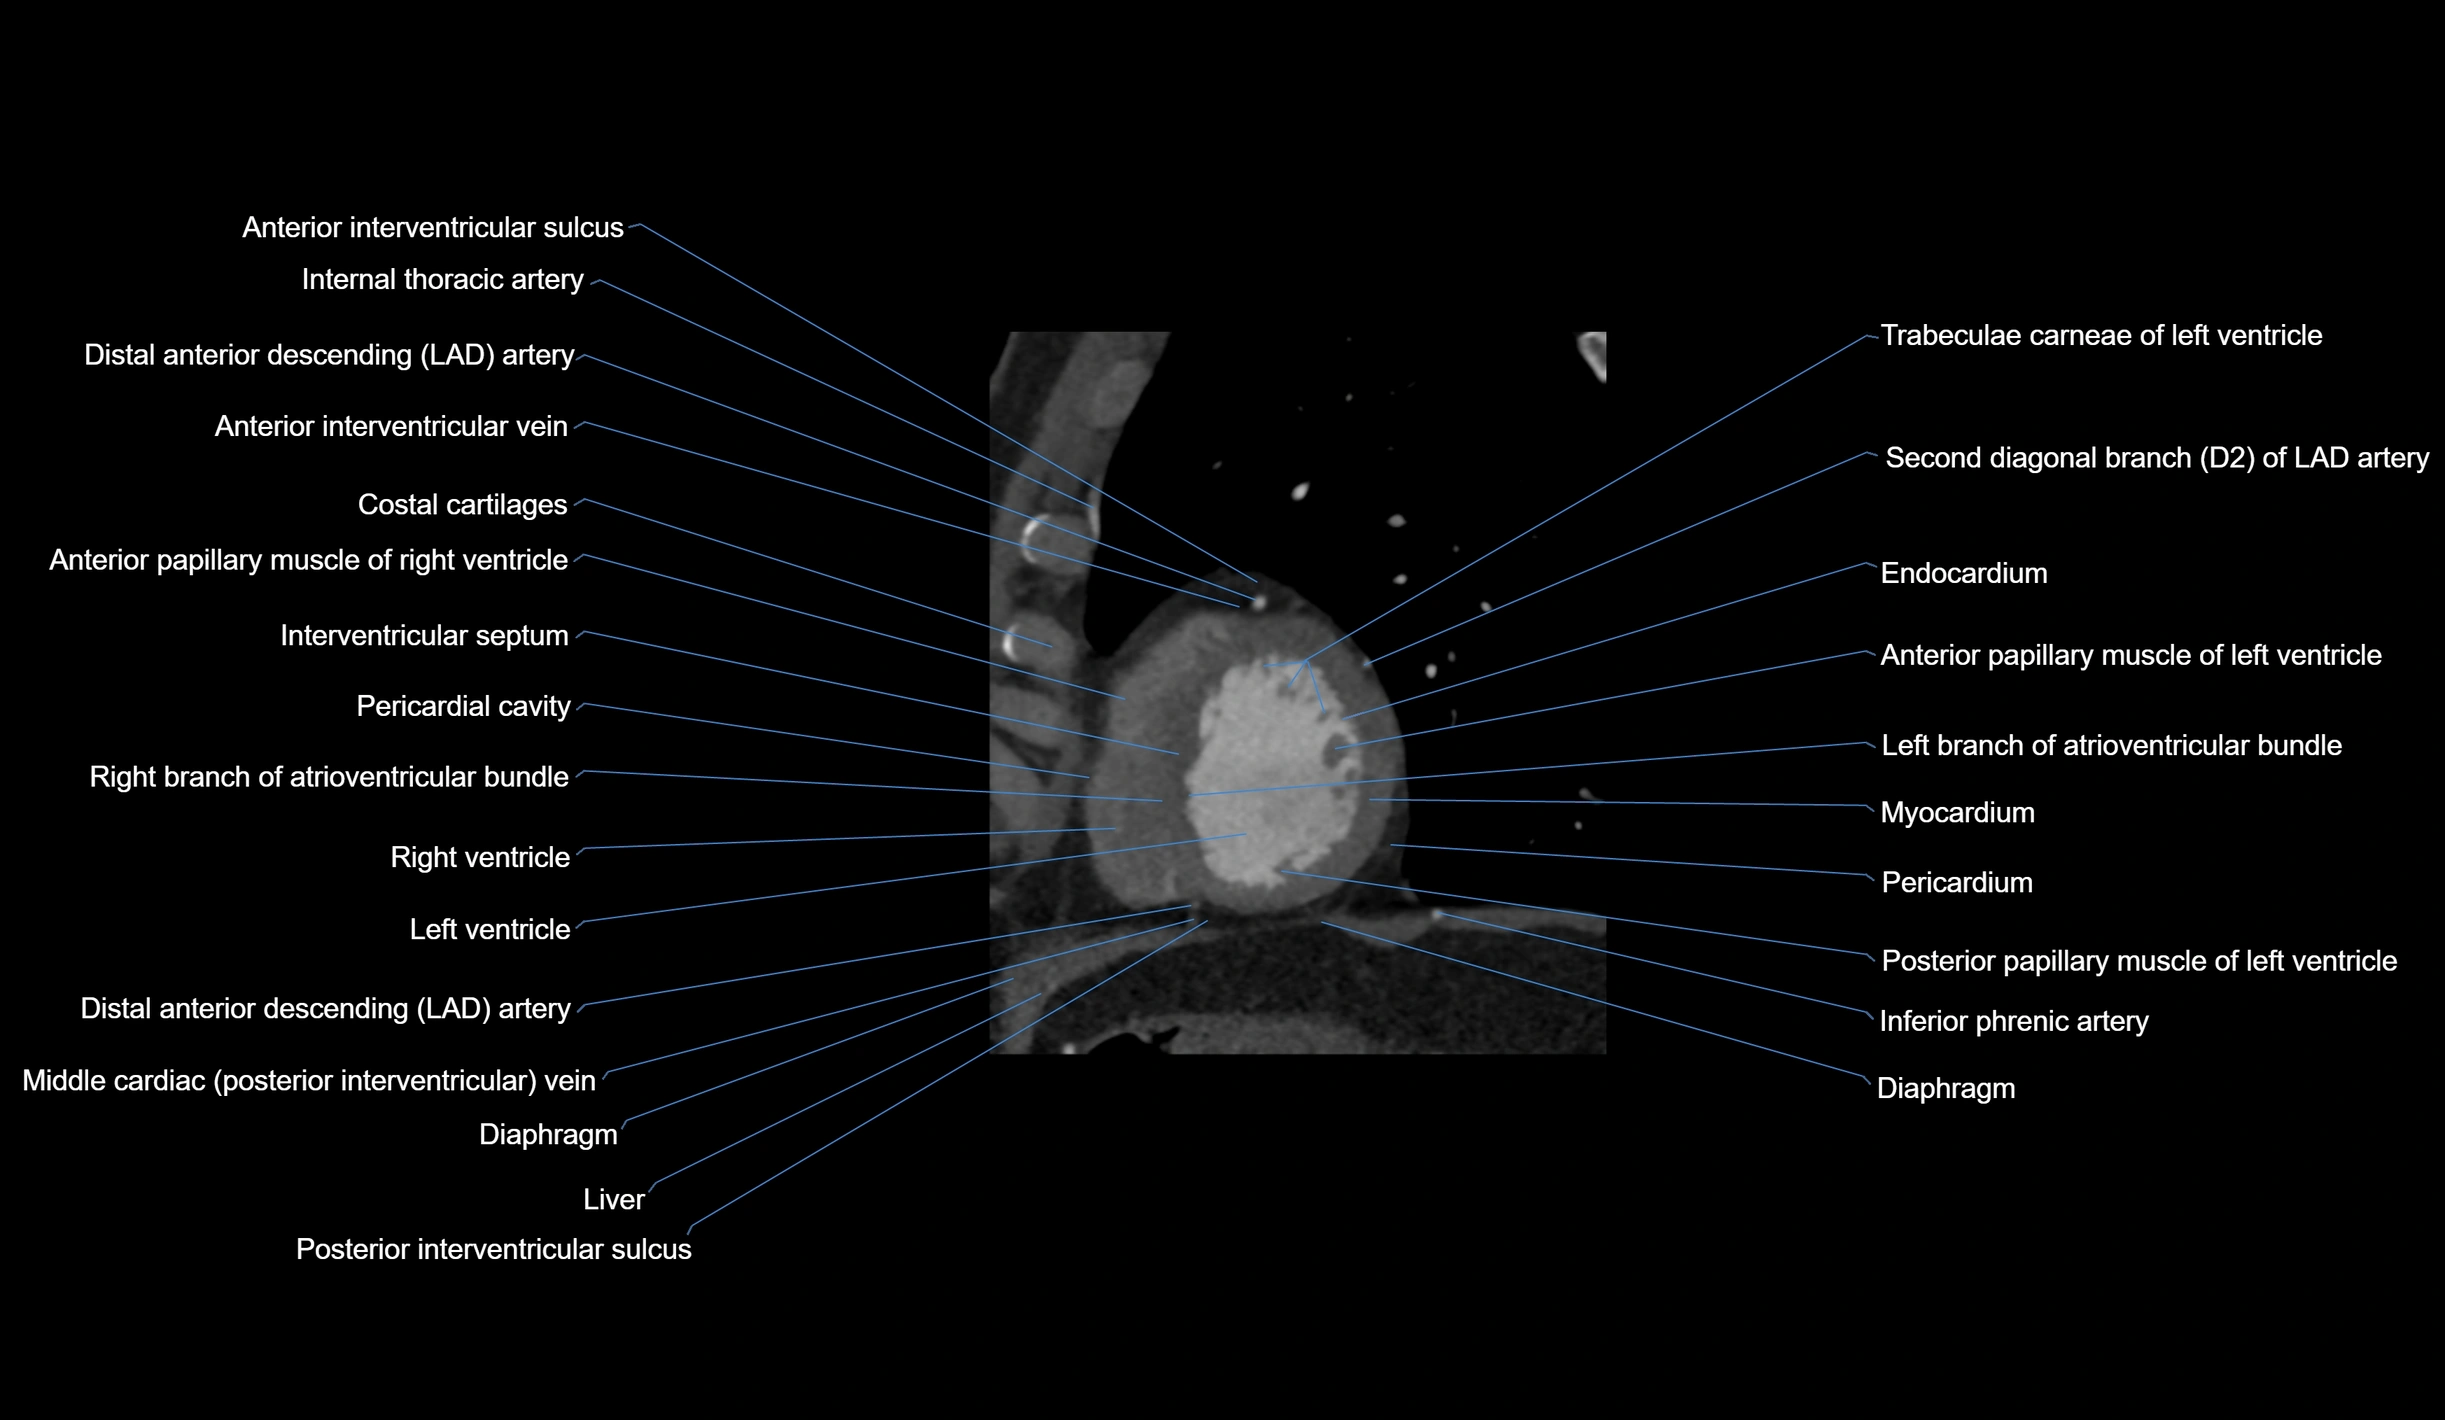

- Anterior interventricular sulcus

- Costal cartilages

- Distal left anterior descending artery (dLAD)

- Endocardium

- Inferior phrenic artery

- Interventricular Septum

- Left branch of atrioventricular bundle

- Left ventricle

- Middle cardiac vein

- Myocardium

- Pericardial cavity

- Pericardium

- Posterior interventricular sulcus

- Posterior papillary muscle

- Right branch of atrioventricular bundle

- Right ventricle

- Second diagonal branch (D2) of LAD

- Trabeculae carneae